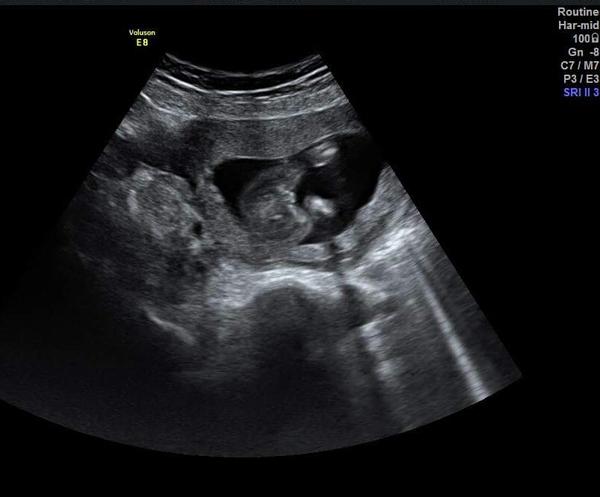

@ikonica Áno tešíme sa veľmi, sme tomu neverili 😄

Ale ja som to tušila, že nosím pod ❤ malú princeznú 🙂